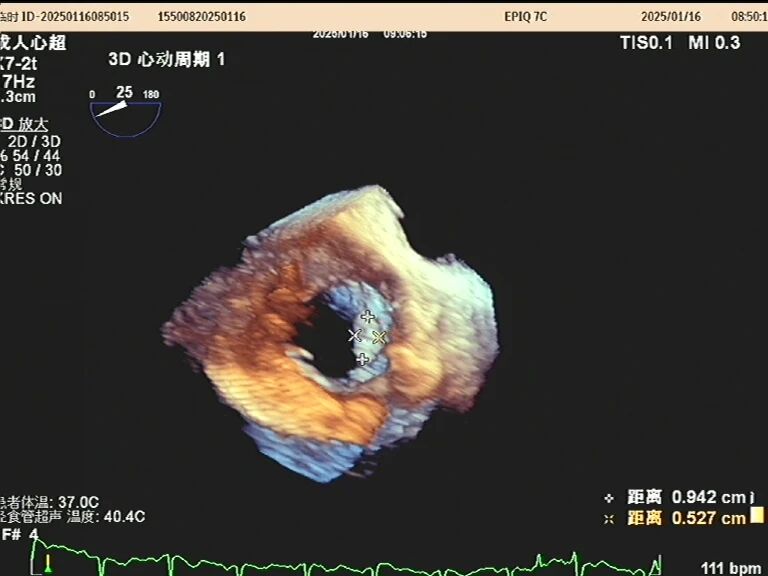

于是,一根如面条般柔软、顶端带着微型摄像头的探头,会从您的口腔缓缓进入食道。这个位置堪称完美,探头能紧贴着心脏,利用超声波为其拍摄一场无死角、超高清的“内部直播”。以前藏在背后的细微结构比如心耳里是否藏有血栓、人工瓣膜是否严丝合缝、心脏瓣膜上的小赘生物,此刻都一览无余。